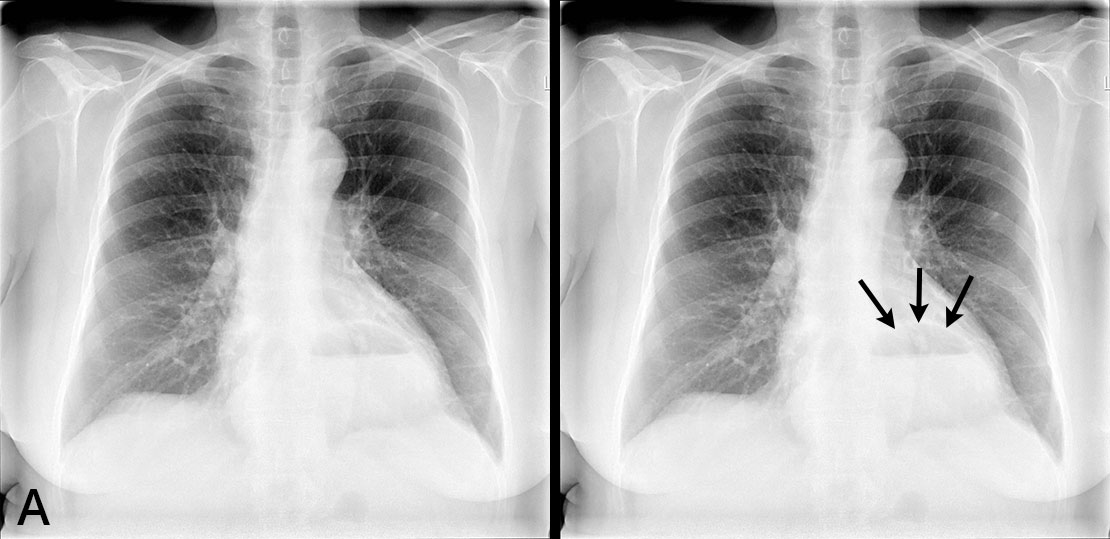

72-vuotias verenpainetautia ja munuaisten vajaatoimintaa sairastava nainen hakeutui tutkimuksiin heikentyneen rasituksensiedon ja hengenahdistuksen vuoksi. Potilaasta otettiin thoraxkuva ensisijaisena ajatuksena hengitystieinfektio tai sydämen vajaatoiminta.

A ja B. Sekä etu- että sivukuvassa ilmeni kookas palleatyrä, jonka sisällä oli ilmakupla. Sydän oli hieman normaalia kookkaampi, mutta keuhkoverekkyys normaalia. Hilukset ja ylämediastinum olivat siistit, eikä keuhkoparenkyymissa näkynyt poikkeavaa. Pleurasopet terävät. Muista tutkimuksista ilmeni, että huomattava osa ventrikkeliä oli hernioitunut mediastinumin puolelle. Vuoden päästä närästysvaiva hankaloitti elämää niin, että tehtiin ruokatorven varjoainekuvaus ja pohdittiin palleatyrän operatiivista hoitoa.